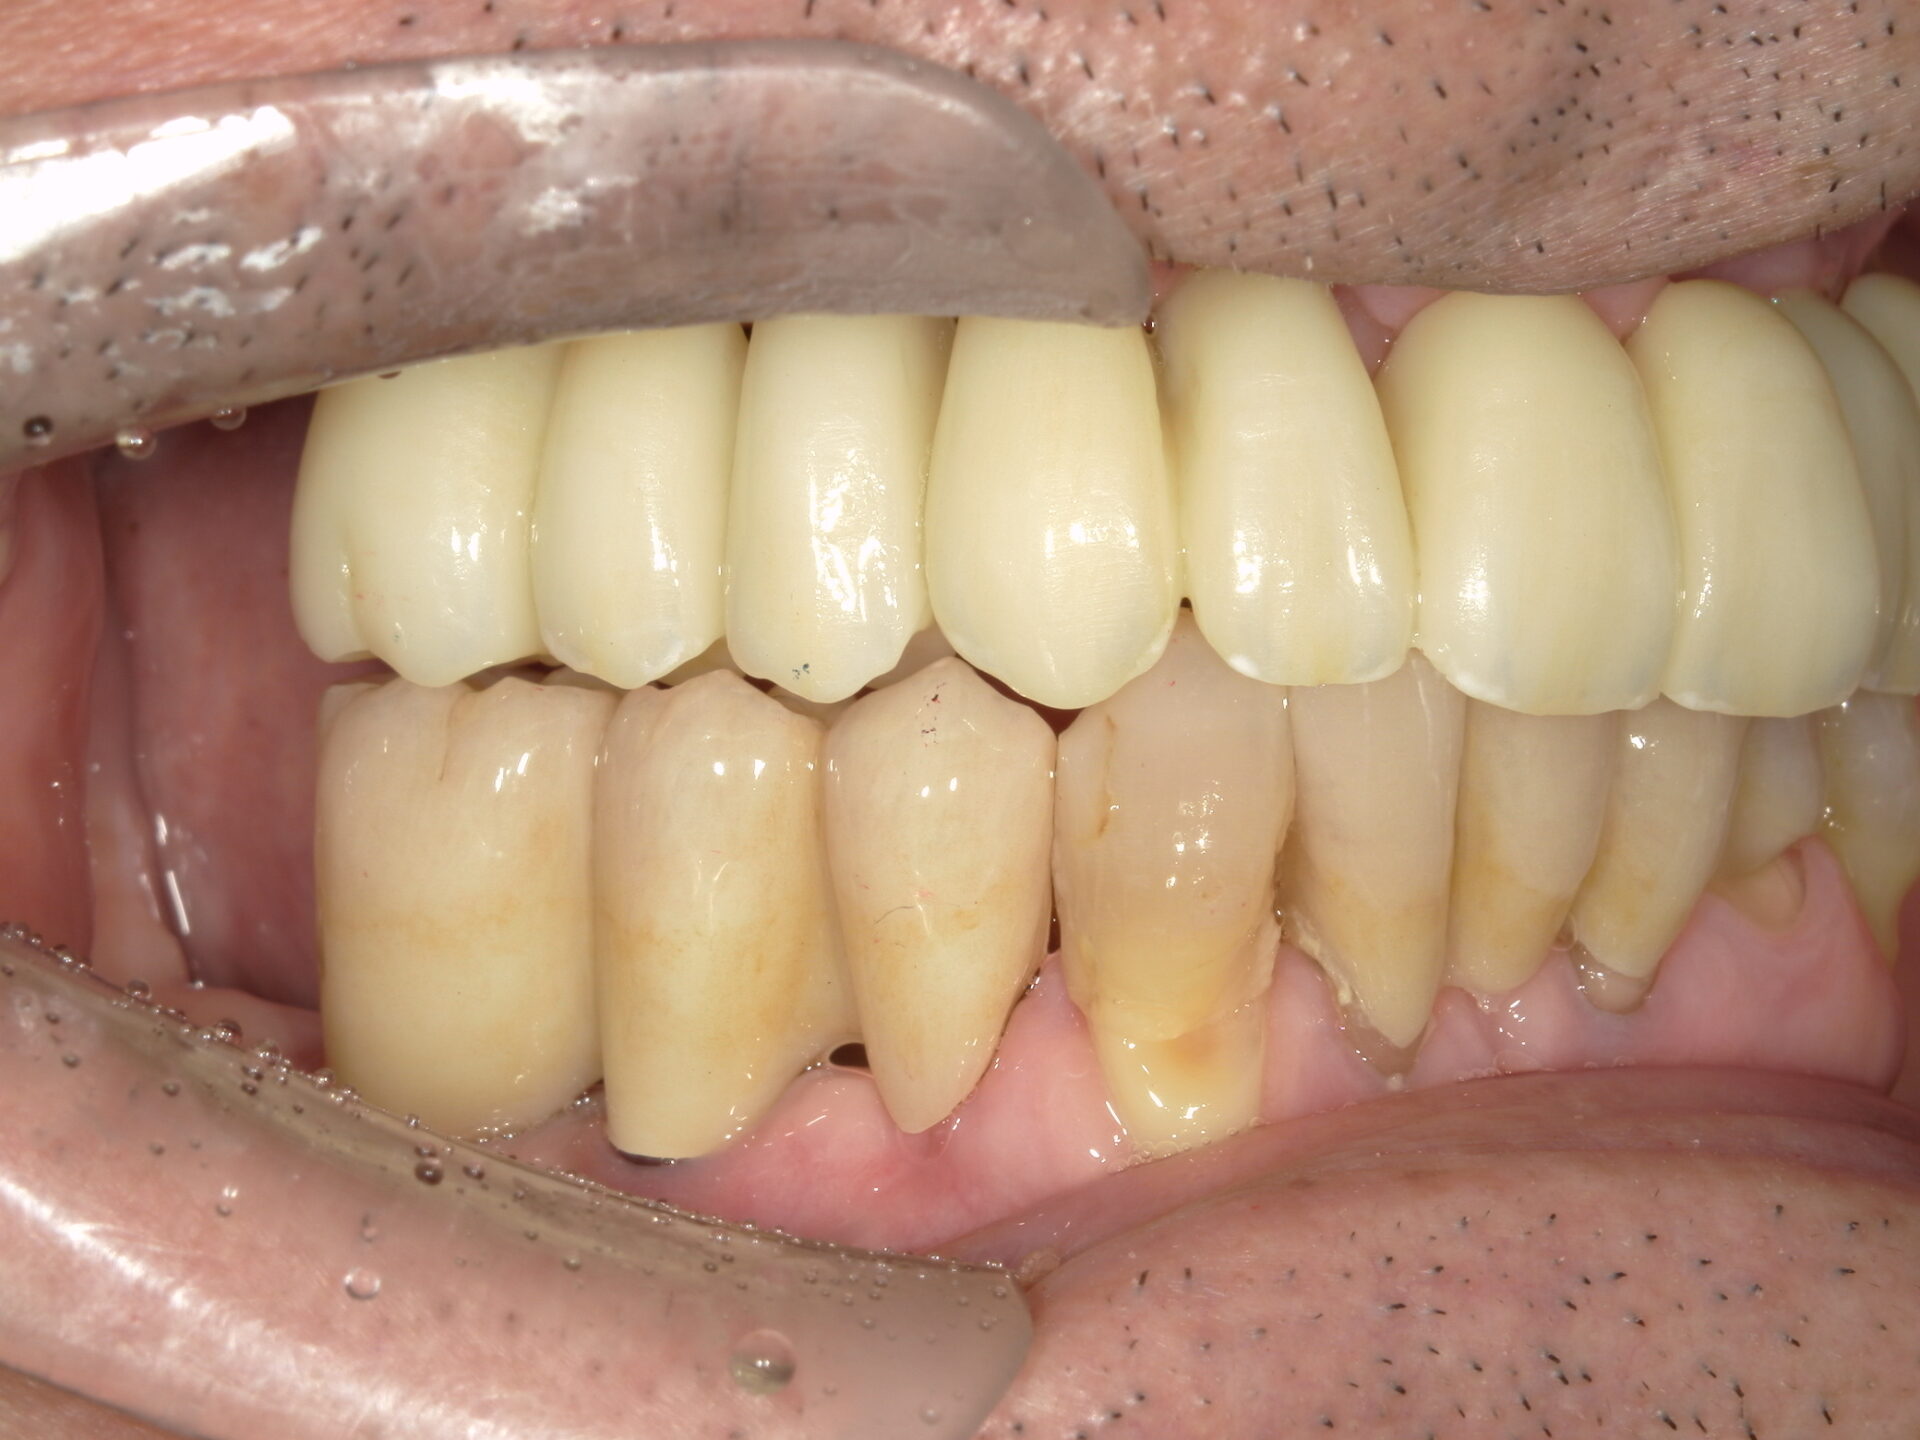

before

患者さんの年齢 50代 男性 症状 何も噛めない 治療内容 インプラント治療(オールオン4) 費用 費用900万(税抜) 治療期間・回数 治療期間2年・通院回数12回 メリット なんでも噛めるようになる 見た目が綺麗 デメリット・リスク 骨造成などで費用が増える場合がある - インプラント治療